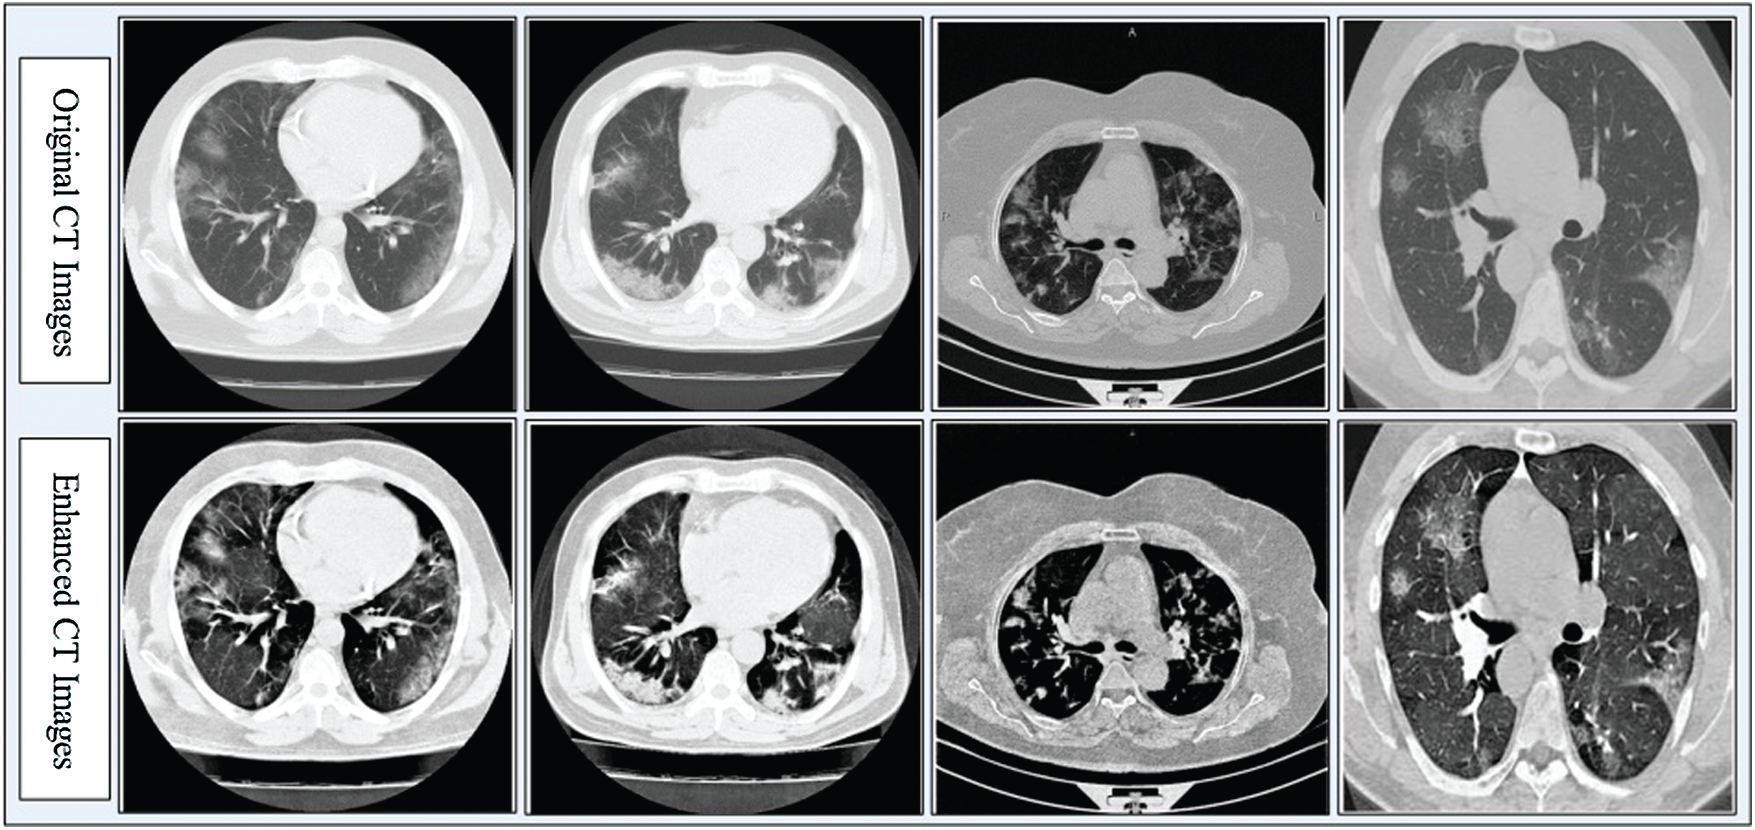

Contrast enhancement improves the quality of input images for useful feature extraction in the pattern recognition step [35]. Here, we implemented a hybrid approach for CT image contrast enhancement. The main purpose of this step was to show a difference between COVID-19 and Pneumonia images. The hybrid approach is based on a new threshold function defined using closing and opening operations, which are applied on original images with a constant parameter. The constant parameter controls the image pixel values and far from zero.

Figure 3: Hybrid contrast enhancement approach results